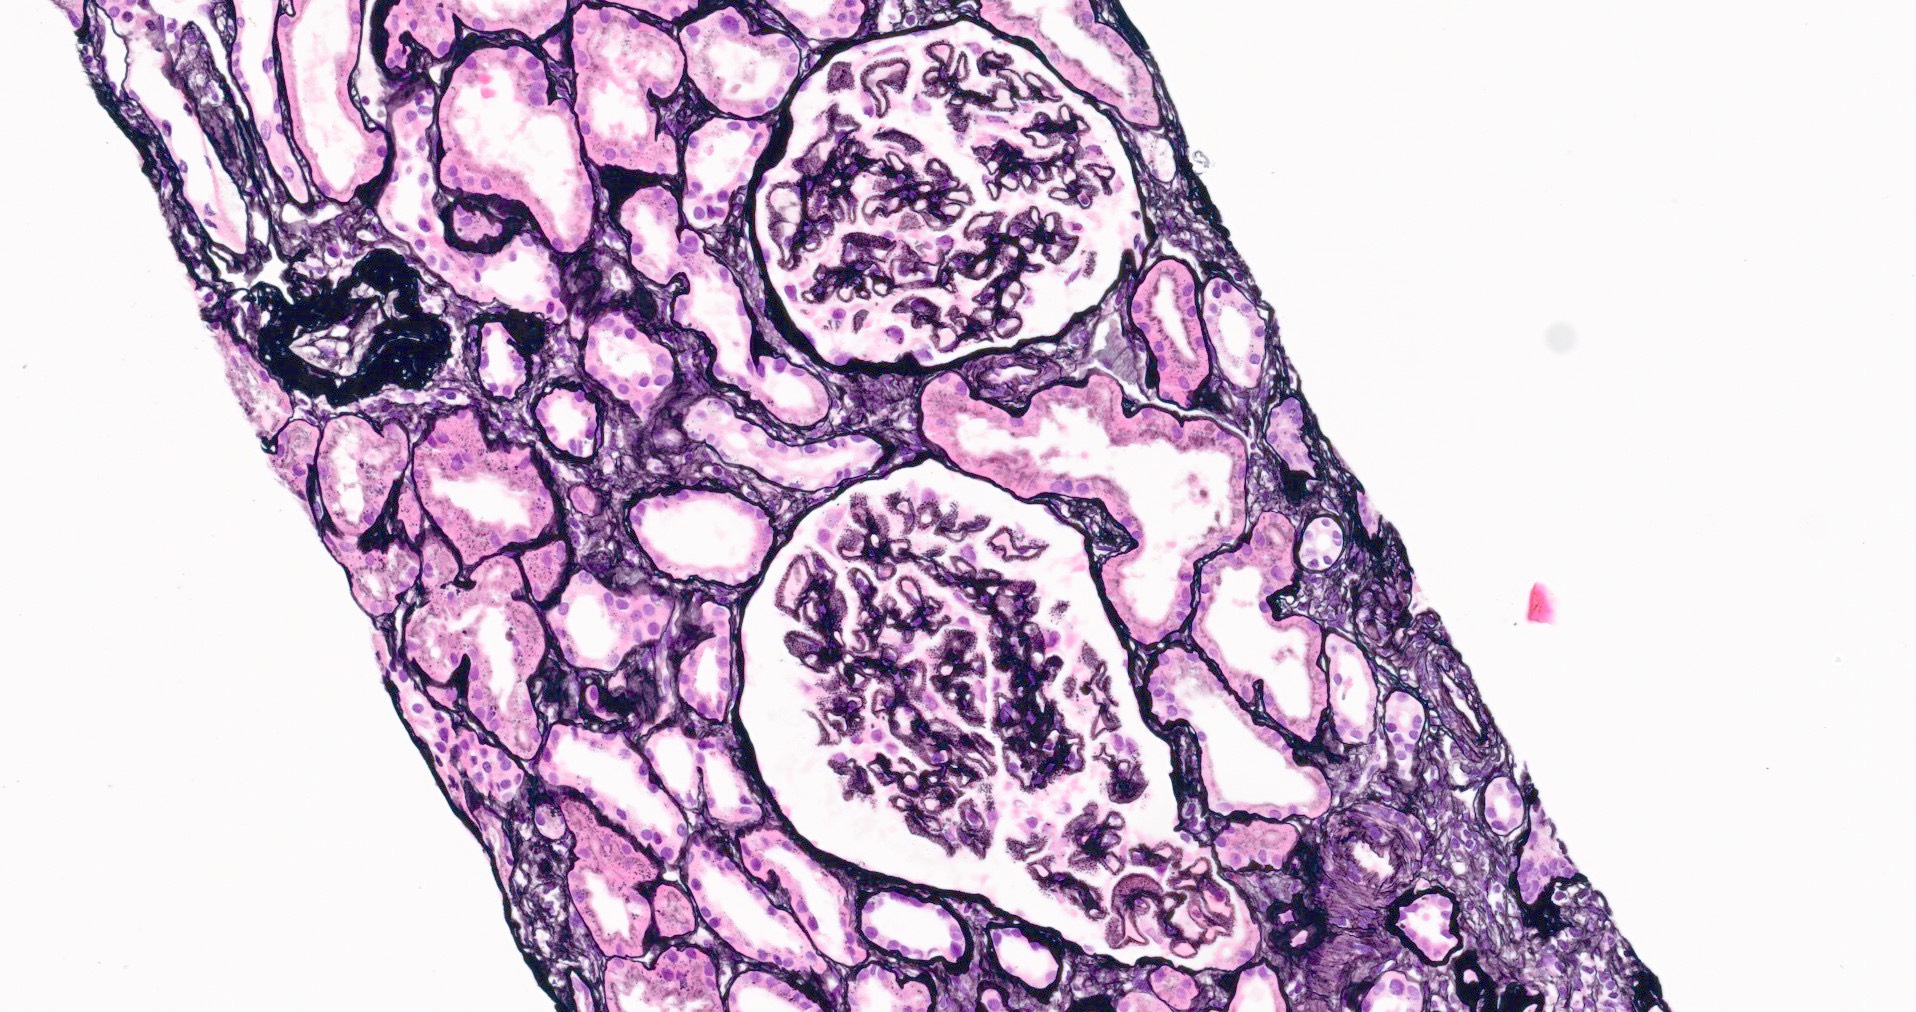

Microscopic (histologic) description

- Thickening of glomerular basement membrane

- Subepithelial spike formation or vacuolated appearance on PAS or Jones silver stain (Colvin: Diagnostic Pathology - Kidney Diseases, 2nd Edition, 2015, Zhou: Silva's Diagnostic Renal Pathology, 2nd Edition, 2017)

Microscopic (histologic) images

- Microscopic description: 18 glomeruli, 1 of these with global sclerosis. Thickening of the glomerular capillary wall. Presence of spikes and internal vacuolizations of the glomerular basement membrane evaluated by silver stain. No evidence of hypercellularity, crescent or necrosis. Fibrosis occupying < 10% of the interstitium.